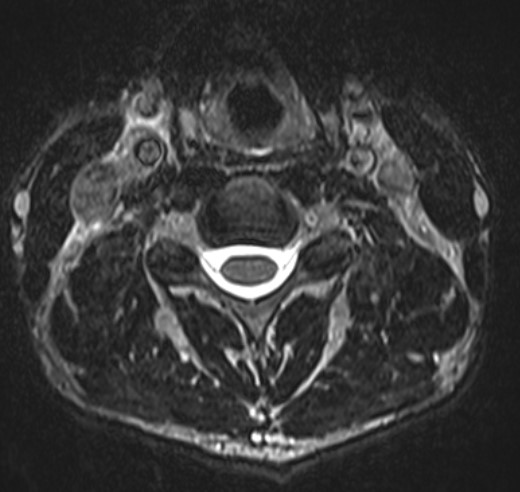

Normal Images Cervical Spine Lateral Xray Cervical Spine CT Cervical Spine MRI Sagittal Cervical Spine MRI Axial Lumbar Spine AP Xray Lumbar Spine Lateral Xray Lumbar Spine CT sagittal Lumbar Spine MRI sagittal Lumbar Spine MRI axial